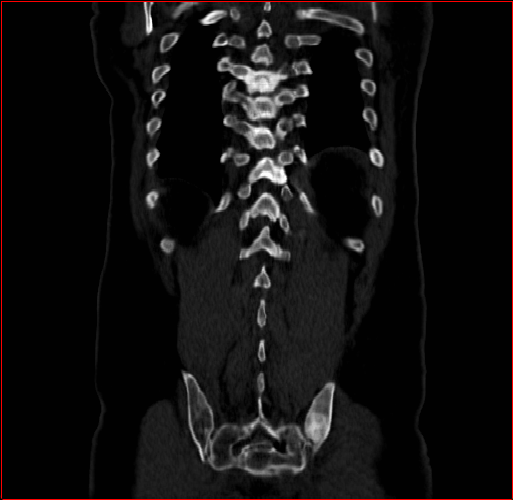

Figure 2: Qualitative comparison across axial (top row), sagittal (middle row), and coronal (bottom row) views. Columns correspond to different methods. MAISI-DDPM and MAISI-v2 in this figure are unconditional synthesis which do not use ControlNet or segmentation maps.

Figure 2 presents representative slices from the axial, sagittal, and coronal planes. GenerateCT (hamamci2024generatect) is a 2D model, so it lacks inter-slice consistency, leading to poor image quality in the sagittal and coronal views. MedSyn (xu2024medsyn) produces noticeably blurry results with mosaic-like artifacts, such as region inside the red box. HA-GAN (sun2022hierarchical) generates visually sharp images but with mosaic-like artifacts, such as region inside the red box. Also, its voxel spacing is not available, which limits its applicability in real-world medical imaging tasks. Moreover, all three methods are restricted to synthesizing small anatomical regions. In contrast, both MAISI and MAISI-v2 are capable of generating high-quality 3D volumes that span larger body regions while preserving fine anatomical details and realistic structure.